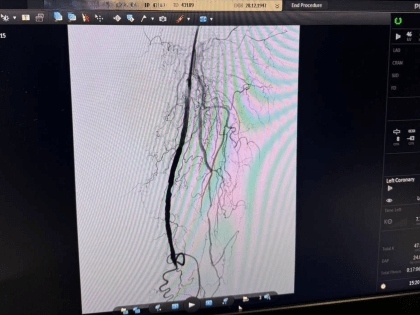

Новый метод баллонной ангиопластики внедрен в Астрахани

В Астрахани успешно применяют минимально инвазивную процедуру для восстановления кровотока в артериях.